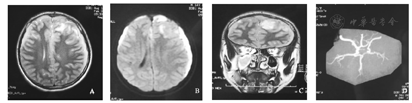

患儿,男,14岁,主因"间断发热、头痛1周,呕吐1 d"于2016年2月7日入院。入院前1周无明显诱因出现发热,体温最高达39.4 ℃,伴有前额阵发性头痛,不伴恶心、呕吐,无抽搐,无视物模糊等不适,外院给予"退热针"治疗,发热及头痛好转,入院前1 d再次出现发热、头痛,伴有喷射性呕吐,5次/d,头痛为持续性,前额部为著,就诊我院,查血常规:WBC 25.08×109/L,中性粒细胞比例89.2%,CRP>210 mg/L,头颅CT显示:硬膜下积液,鼻窦炎。患儿既往体健,否认外伤史。入院查体:精神欠佳,反应弱,表情痛苦,能简单对答,自行步入病房,咽充血,双侧扁桃体Ⅱ度肿大,可见脓性分泌物,颈抵抗阳性,右侧巴氏征阳性。患儿入院后病情进展迅速,出现意识障碍,进入浅昏迷状态。入院后完善辅助检查:血常规:WBC 18.95×109/L,中性粒细胞比例91.9%,CRP>200 mg/L;血生化:ALT 1 123.6 U/L,AST 1 108.5 U/L,Na+129 mmol/L;脑脊液:WBC 48×106/L,多核为主,蛋白定量1 759.7 mg/L;头颅MRI增强扫描(图1)显示:双侧颅板下方、大脑镰前部可见长T1、长T2信号,左侧为著,左侧额叶脑实质可见片状长T1、长T2信号,增强可见脑膜异常强化;左侧脑室受压,中线轻度右移;MRA:左侧大脑中动脉分支较对侧稀疏,鼻窦炎、右侧尤为显著。临床诊断为:(1)化脓性脑膜炎、脑脓肿、多发性硬膜下积脓;(2)急性化脓性扁桃体炎;(3)鼻窦炎。入院后给予美罗培南+万古霉素联合抗感染,免疫支持、抗炎及降颅压治疗,并与入院后第3天行左侧额颞顶硬膜下积脓钻孔引流术,术中引流脓液20 ml,术后复查头颅CT提示左侧硬膜下积脓较前减少,术后引流液培养提示中间型链球菌,药敏提示万古霉素敏感。患儿体温逐渐正常,意识状态逐渐清醒。入院第16天复查腰椎穿刺,提示脑脊液常规、生化及涂片大致正常。入院第26天复查头颅MRI提示右侧硬膜下积液范围扩大(图2),于入院第27天行右侧额颞硬膜下积脓钻孔引流术,术中引流脓液20 ml,术后复查头颅MRI提示右侧硬膜下积脓明显减少,引流液未见细菌生长,停用静脉抗生素后观察患儿无发热,无头痛、抽搐等不适症状,生活基本自理,住院36 d,好转出院,出院后3周复查头颅核磁共振提示病变较前好转,可正常生活。